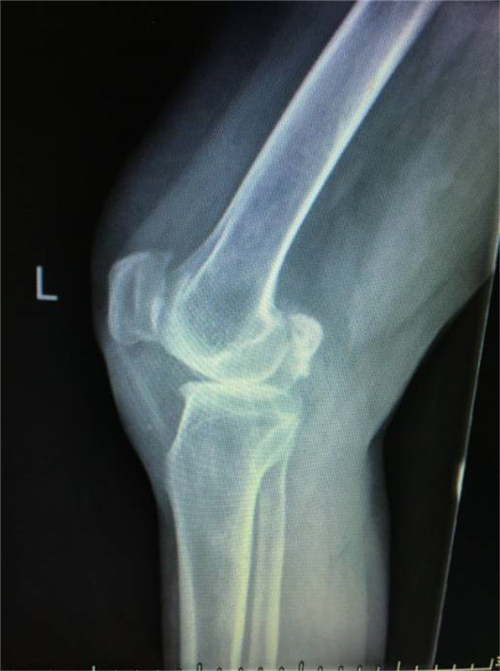

得知郴州市第四人民医院骨科掌握了这一手术技术,便前来就诊。谭主任接诊到该患者后,对其进行了详细的体格检查,发现其左膝关节僵直,屈伸活动不能,负重时膝关节疼痛明显加重,膝关节X线片提示膝关节退变严重,关节间隙明显变窄,并有游离体形成,诊断为左膝关节重度骨关节炎并关节僵直,有明确的膝关节置换手术指征。

术前X线